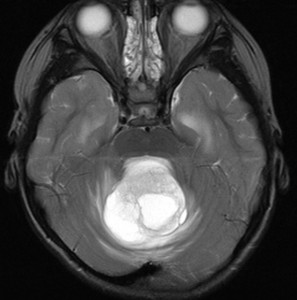

第4脳室腫瘍のMRI像

左は脳幹部腫瘍(退形成性神経節膠腫),右は小脳腫瘍(毛様細胞性星細胞腫)です。どちらも第4脳室を埋め尽くすように発育しています。これらはどちら側から発生したかが明瞭な例ですが,第4脳室腫瘍の中には脳幹部からか小脳からか解らないものもあります。でも多くは小脳側からです。脳幹部側からで注意しなければならないのは上衣腫と血管芽腫です。